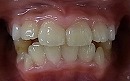

今回の場合、歯並びが悪い原因は 上顎が小さい事 でした。

拡大 矯正前 矯正後

診査・診断の結果、

上顎の大きさを約10ミリ大きくしなくてはならないことがわかりました。

今回の症例は、約6カ月ほどで改善しています。

しかし、拡大だけで将来の歯並びが良くなる訳ではありません。